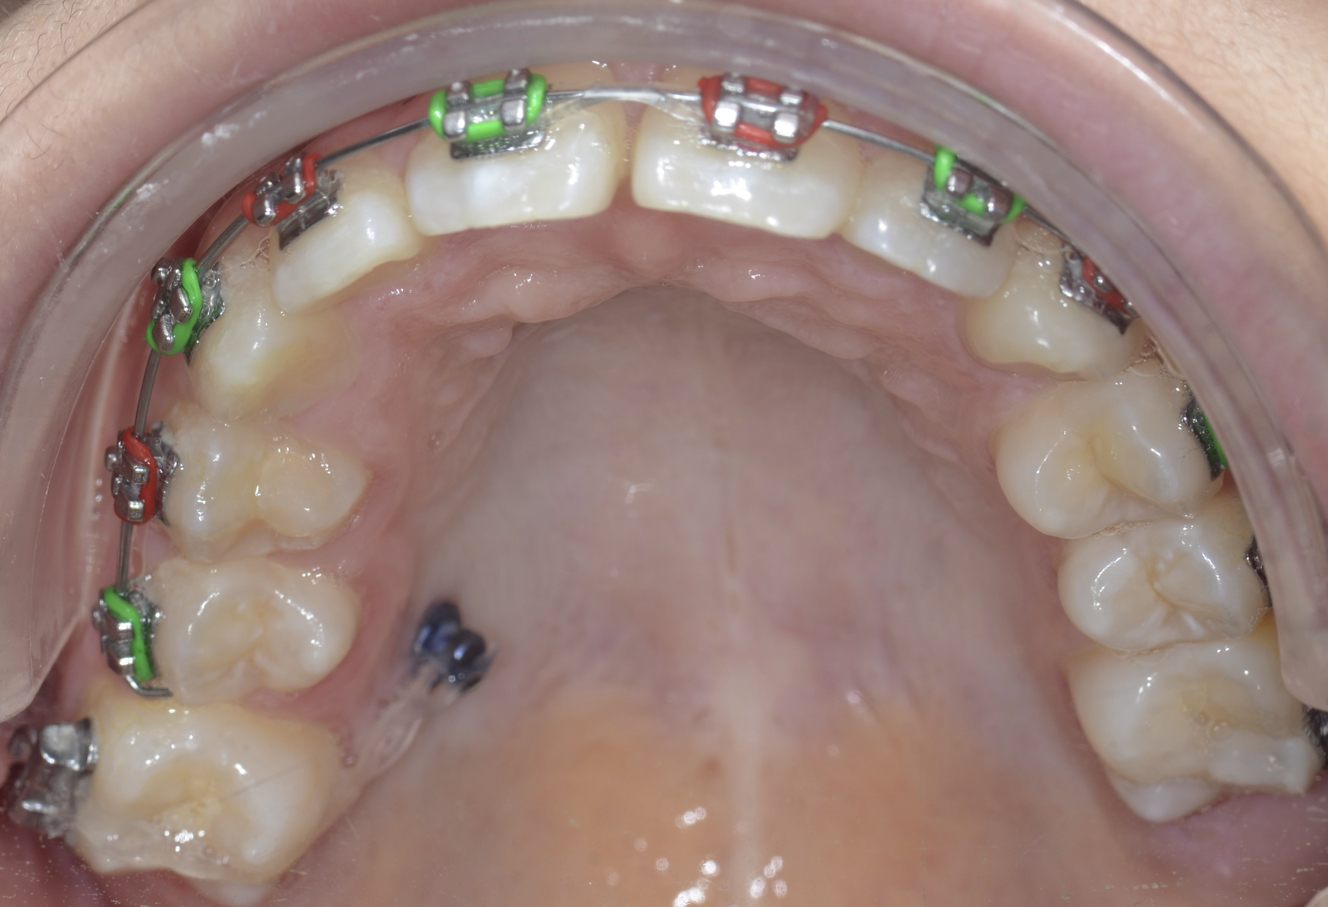

There may be interferences unaccounted for or unpredicted movement during activation requiring intervention to mold the generate during the consolidation phase. The consolidation period usually spans 8 weeks after activation is deemed complete. During consolidation and postoperatively, the occlusion must be idealized and the patient should be closely followed by the orthodontist. Often there is significant occlusal adjustment required to establish a stable bite after activation is complete. Note that the actual vector observed often differs from the one planned presurgically, and can be affected by the biomechanics of the individual device, the differences in individual mandibular anatomy, neuromuscular effects, and external force. Fixed braces can be used for patients with adult dentition, whereas bonded splints with hooks may be necessary in patients with short clinical crowns or multiple missing teeth. Temporary anchorage devices (TADs) or intermaxillary fixation screws are useful in all patients for the application of bone-borne forces ( Figs. 5 and 6 ). The forces are ideally distributed over the basilar portion of the jaws to avoid extrusion of individual teeth, and TADs achieve this effectively. Interdental orthodontic elastics used in conjunction with any of the appliances mentioned earlier can assist in molding the bony generate during both the activation and consolidation phases. Heavy elastic forces should be applied immediately during the consolidation phase because they are deemed ineffective at idealizing the alveolus once the bone has consolidated. It is recommended that the distractors remain while elastic forces are being used during the full consolidation period; if removed too early, there can be bending of the bony generate and buckling from the weakness. Interestingly, orthopedic and orthodontic forces are more efficient and effective during these healing phases, likely because of increased bone metabolism after surgical trauma. This finding results in a window of opportunity during which time orthodontic visits should be frequent in order to accomplish treatment goals.